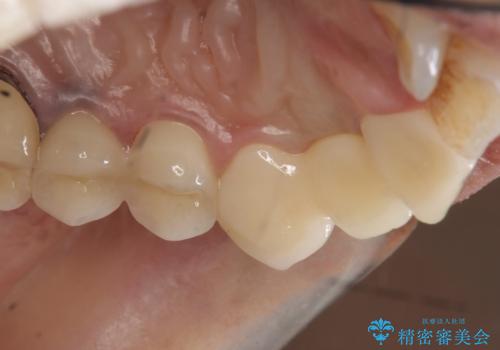

左上2番目の歯は歯根が破折してため抜歯し、左上123のブリッジによる欠損補綴を行いました。

左上4、5番目の歯は根尖病変を認めたため再根管治療を行い、オールセラミッククラウンによる補綴を行いました。

今回用いたオールセラミッククラウンは、ジルコニアフレームという白い素材の上にセラミックを盛っているため審美性が非常に高いのが特徴です。

またジルコニアは人工ダイヤモンドの材料にも使われているほど高い強度を持っており、そのためオールセラミッククラウンは審美性だけでなく、奥歯やブリッジの補綴も可能とするクラウンです。